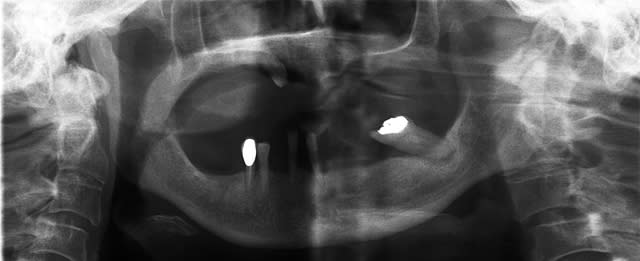

voici la pano

Elmerich jeannine pttrvl - Eugenol

3f3boxni50k58rq7e9ce9ddqrxgk - Eugenol

une téléradio de profil et extraction-implantation et mise en charge immédiate sans extension de 5 implants dans la symphyse.

2-L'os au distal des mentoniers semble pas mal, mais la radio est très déformée...il est contorsionniste ton patient ?

3-Pour le haut, quel est le plan ? Implants ?